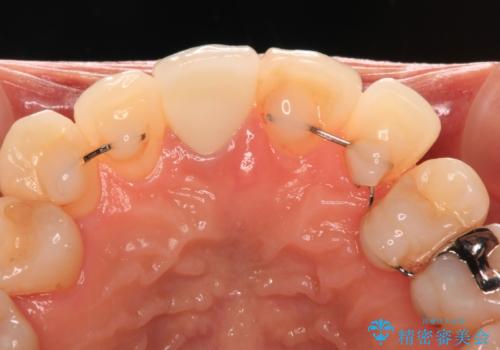

失活により変色した前歯 オールセラミッククラウンによる審美歯科治療

- 前歯の変色を気にして来院された患者様です。

ラミネートベニアによる治療を以前受けていたものの、神経組織が失活して以降、徐々に変色してきたとのことでした。

オールセラミッククラウンにて補綴治療を行うこととしました。